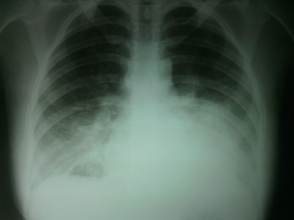

Բաժանմունքի վարիչը բացատրել է, որ այդ վիճակով դուրս գրվել չիկարող. անհրաժեշտ է կատարել ռենտգեն հետազոտություն, որից հետո որոշել դուրս գրման հարցը: Համայցից հետո հիվանդը ենթարկվել է ռենտգեն հետազոտության, որի ժամանակ հայտնաբերվել է թոքաբորբ: Կրկին կատարվել է թերապևտի կոնսուլտացիա, որը թոքերում լսել է թացխզոցներ, առավելապես՝ ձախից: Հիվանդին և նրա ամուսնուն բացատրվել է, որ կարիք կա հետագա բուժումը շարունակելու Երևանի 3-րդ կարգի մանկաբարձական բաժանմունքներից որևէ մեկում: Տրվել է ուղեգիր: Հիվանդի ամուսինը ցանկացել է իր մեքենայով տեղափոխել հիվանդին Երևան: Միաժամանակ նշենք, որ «Զարիշատ (Արամ) Մարտին Մկրտչյանի անվան Արմավիրի ԲԿ» ՓԲԸ մանկաբարձական բաժանմունքում հիվանդը մնացել է 39 ժամ, և Երևան գնալու պահին նրա վիճակը եղել է բավարար:

Կից տեղադրվում է նաև «Զարիշատ (Արամ) Մարտին Մկրտչյանի անվան Արմավիրի ԲԿ» ՓԲԸ-ում կատարված ռենտգեն նկարը: